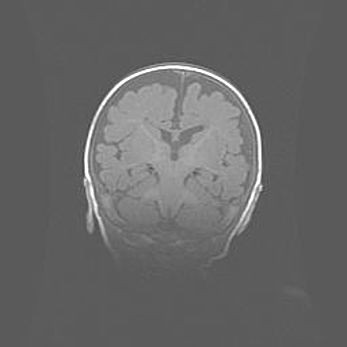

Наружная гидроцефалия с возможной атрофией височных областей.

Возраст: 28 дней

Вес: 3670 г

Пол: мужской

Окружность головы: 38 см

Срок гестации: 40 недель

Гидроцефалия головного мозга у новорожденных – это заболевание, которое характеризуется скоплением избыточного количества спинномозговой жидкости в желудочковой системе головного мозга в результате затруднения её перемещения от места выработки к месту поглощения в кровеносную систему или вследствие нарушения абсорбции. При открытой наружной форме гидроцефалии у новорожденных расширяются и переполняются субарахноидные пространства.

При нормотензивных  формах,  которые,  как  правило,  являются  следствием  перенесенных ишемических  повреждений  паренхимы  мозга,  возможно  сочетание микроцефалии  с нормотензивной гидроцефалией. В основе данных изменений лежит атрофия больших полушарий с преимущественной  локализацией  в  лобно-височных  областях.